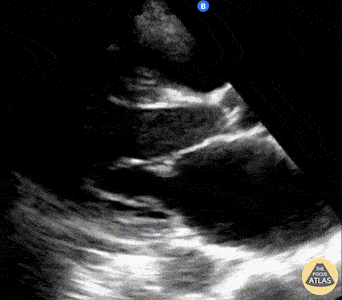

A 60-year-old female presented with palpitations; found to have atrial fibrillation. Parasternal long POCUS was notable for both an enlarged LA as well as depressed LV systolic function. These concurrent diagnoses enabled initiation of proper rate-control while also being mindful to not worsen HF exacerbation (avoiding b-blockade). The combination of A.fib as well as LV dysfunction also made this patient particularly high risk of thromboembolic events; she was therefore also initiated on therapeutic anticoagulation. Shahad Al Chalaby, MD. PGY-2, Internal Medicine Highland Hospital, Almeda Health System, Internal Medicine Residency Program. CA, USA @shahad_Chalaby